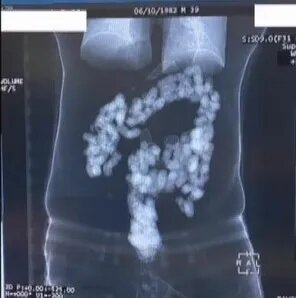

Mədəsində 2 kiloqram heroin keçirmək istəyənlər saxlanılıb.

Həbs olunan R.Y. və H.F. adlı şəxslər mədəsində 244 kapsulda 2 kiloqram heroin keçirtmək istəyiblər.